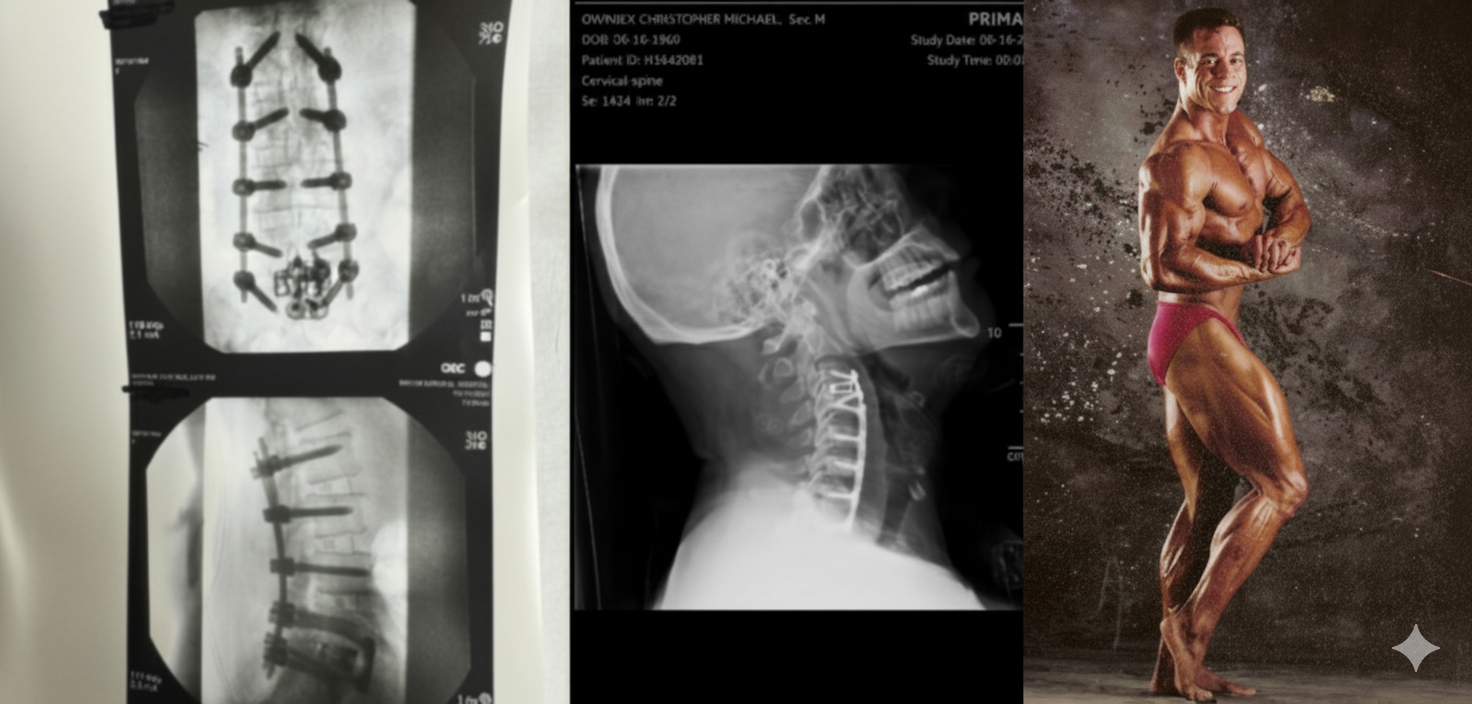

He’s fought through multiple back and neck surgeries, battled setbacks that would’ve stopped most people, and carried the responsibility of raising two boys 24 years apart, with two grandchildren depending on his example. Slowing down was never an option.

2024 was his year of full neck and back fusion — and his comeback.

Now in his 50s, Chris chose the harder road: recommitting to training smarter, eating with intention, and rebuilding his body with purpose. His life is proof that after 40, strength isn’t just possible — it’s essential.